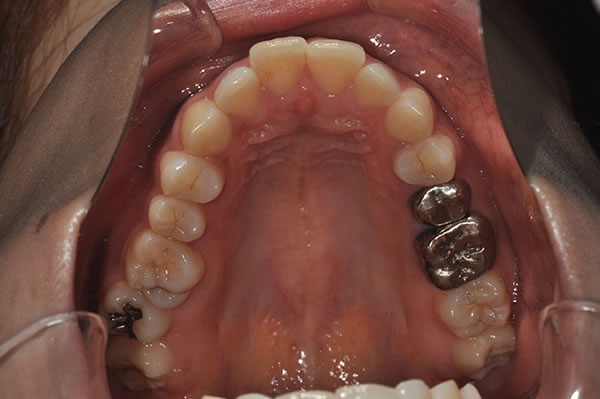

上顎前突症の治療例

上顎前突症(出っ歯)の矯正症例 ケース01

| 治療前(初診) | 治療後 | |